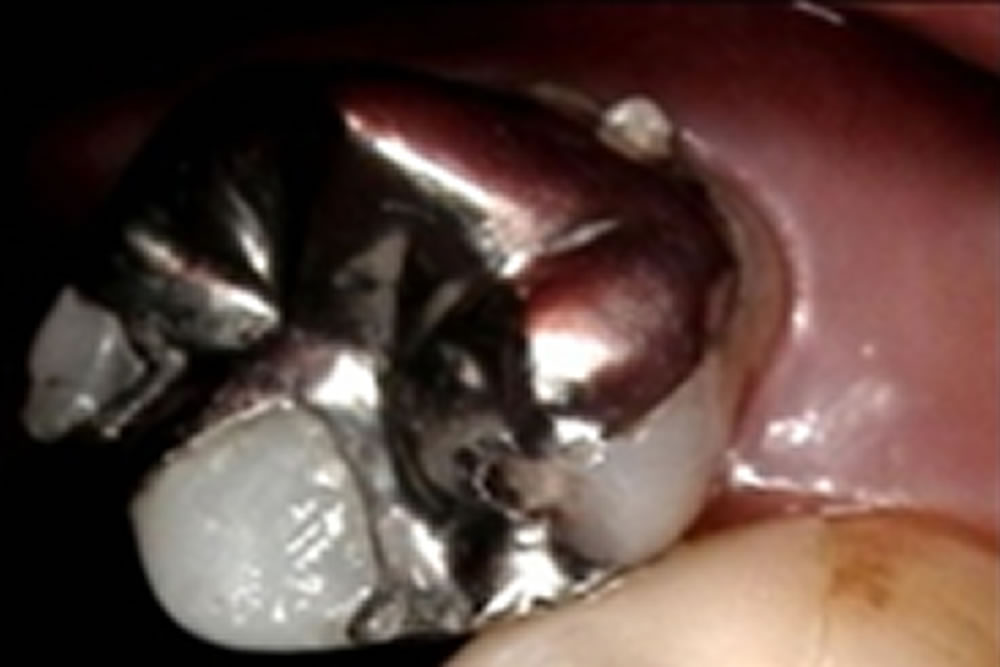

保険のつめ物をセラミックオンレーに変更した症例②

保険のつめ物をセラミックオンレーに変更した症例 こちらの患者さまは、保険のインレーが入っている歯と被せ物の境目に段差が生じていることが、レントゲン写真と口腔内診査にて確認できました。 今まで他の歯も保険のものからセラミッ […]